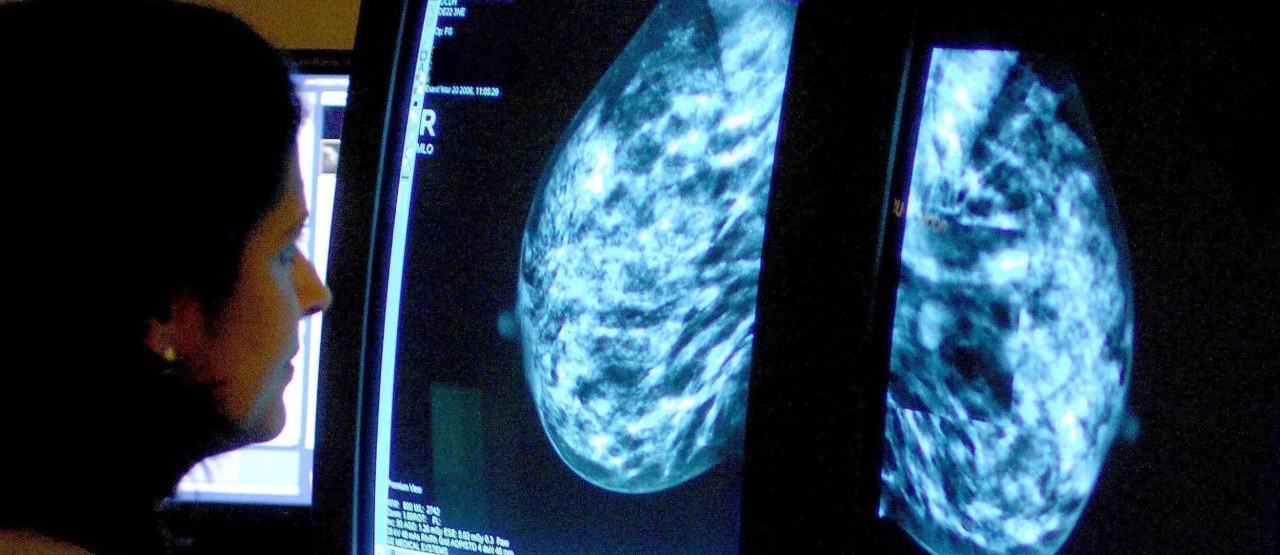

Nie zawsze tak jest, dlatego specjaliści zastanawiają się nad tym jak to zmienić. Zwłaszcza, że mamy możliwości nowoczesnego leczenia i indywidualnego podejścia - ale problemem wciąż jest wykrywalność raka piersi, który jest najczęstszym nowotworem u kobiet i wciąż zbyt wiele pacjentek umiera z jego powodu. Tymczasem wcześnie wykryty i odpowiednio leczony może być chorobą przewlekłą jak nadciśnienie czy cukrzyca. Trzeba więc zwiększać zainteresowanie profilaktyką- choćby badaniami przesiewowymi dla osób po 45 roku życia.

Żeby osiągnąć spadek umieralności na raka piersi musi 70 proc kobiet wziąć udział w tym badaniu, a w Polsce bierze w nim udział tylko 32 proc. Dlatego jesteśmy na siódmym miejscu od końca w Unii Europejskiej, jeżeli chodzi o przeżycia - tłumaczy doktor Marek Budner z Helios Klinikum w Niemczech.